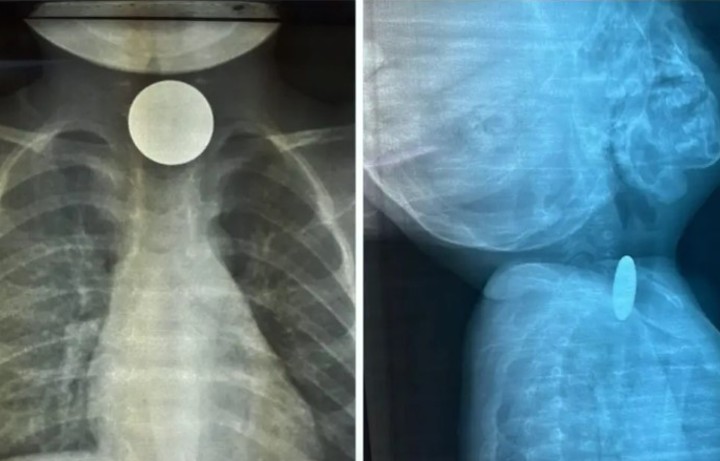

رابغ ہسپتال میں سکہ نگلنے والے دو سالہ بچے کو بچالیا گیا